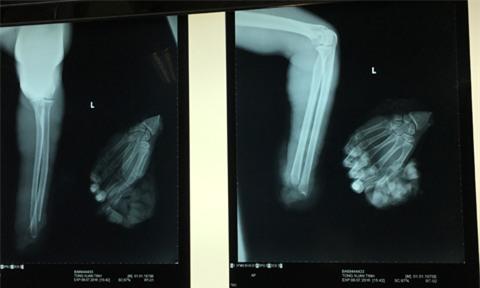

Nam công nhân bị máy cưa gỗ cưa đứt lìa cổ tay trái - Ảnh 2.

Bàn tay của nạn nhân bị đứt lìa (phim Xquang)